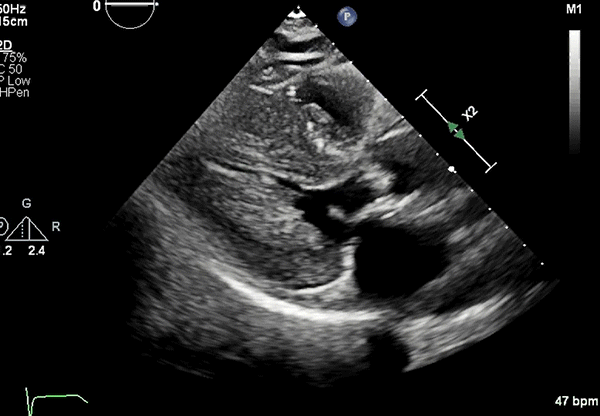

Echocardiography: Severe concentric LVH (interventricular septum diameter 1.7 cm, left ventricular [LV] posterior wall diameter 1.8 cm), small LV cavity size, hyperdynamic LV function with LV ejection fraction 75% (Figures 2, 3)

PLAX view showing LVH.

LVH = left ventricular hypertrophy; PLAX = parasternal long-axis.